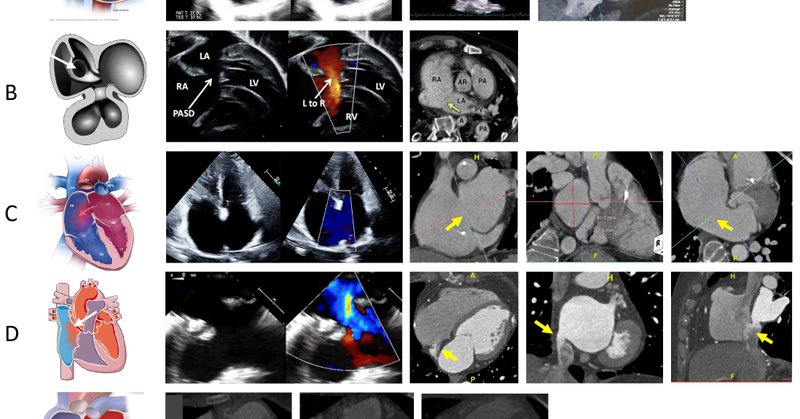

#Sharing is learning When one thing goes wrong… suddenly everything follows. Complications everywhere! 😩🧐🧐🥹🥹😇😇😡😡How many can you spot??

Apical displacement of tricuspid valve with plastering of septal & posterior leaflets to IVS.Sail-like anterior leaflet,Ebsteinoid TV morphology. Large primum ASD with moderate MR (not shown). Rare echo clip of Ebstenoid TV in partial AVSD. #echofirst #CHD #PediatricCardiology